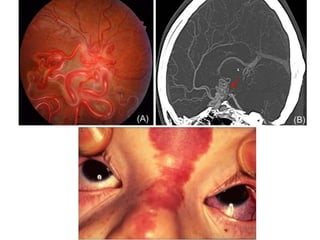

HEMANGIOBLASTOMAS

• Most frequently observed in

VHL

• Sporadic hemangioblastomas

vs VHL disease–associated

• Mean age at presentation is 29

years

• Unpredictable growth pattern - “stuttering”

• Surgery for symptomatic or rapidly growing

lesions

• Preoperative embolization may help to facilitate

surgery by decreasing tumor vascularity

• Hemangioblastomas of the brainstem and spinal

cord can be resected safely

• Preoperative neurological function - best

predictor of postoperative neurological outcome

• Retinal capillary hemangioblastomas and

endolymphatic sac tumors, do not typically

necessitate neurosurgical care

HEMANGIOBLASTOMAS • Most frequentlyobserved in VHL • Sporadic hemangioblastomas vs VHL disease–associated • Mean age at presentation is 29 years

• Unpredictable growthpattern - “stuttering” • Surgery for symptomatic or rapidly growing lesions • Preoperative embolization may help to facilitate surgery by decreasing tumor vascularity • Hemangioblastomas of the brainstem and spinal cord can be resected safely • Preoperative neurological function - best predictor of postoperative neurological outcome

• Retinal capillaryhemangioblastomas and endolymphatic sac tumors, do not typically necessitate neurosurgical care

Sturge-Weber Syndrome (Encephalotrigeminal Angiomatosis) •Sturge-Weber syndrome - skin and the nervous system involved • Most cases, however, seem to be caused by a somatic mutation – Unilateral facial angioma (port-wine stain) – Ipsilateral parieto-occipital leptomeningeal venous angiomatosis – Underlying cortical atrophy – Calcifications in cortical layers – Cystic and enlarged choroid plexus. – Angiomas occasionally in the eye – Increased scleral venous pressure reduces outflow of aqueous humor and may produce glaucoma or buphthalmos

• #67 Unilateral facial angioma (port-wine stain) Ipsilateral parieto-occipital leptomeningeal venous angiomatosis The ipsilateral brain underlying the meningeal abnormality shows cortical atrophy, with calcifications in the second and third cortical layers, and often a cystic and enlarged choroid plexus. Angiomas occasionally may be seen in the eye as well as in other parts of the body along the distribution of sensory nerves. In addition, increased scleral venous pressure reduces outflow of aqueous humor and may produce glaucoma or buphthalmos.